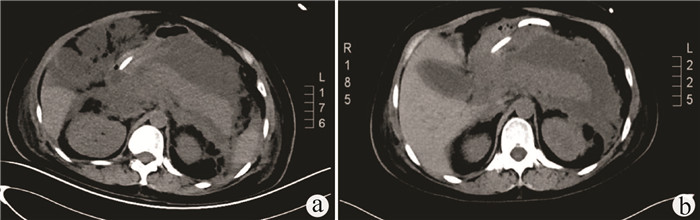

经正中裂联合左右侧入路完整切除肝尾状叶治疗小儿肝泡型包虫病1例报告

李汗, 侯立朝, 王海久, 王聪, 樊海宁

2022, 38(2): 426-429. DOI: 10.3969/j.issn.1001-5256.2022.02.033

摘要(1140) HTML (288) PDF (3527KB)(46)

摘要: